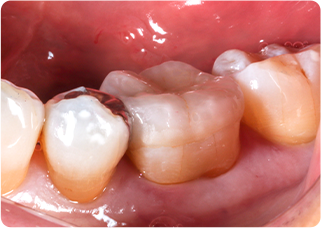

精密根管治療④

術前

術後

| 主訴 | 奥歯で噛むと痛い |

|---|---|

| 治療期間/回数 | 1ヵ月、3回 |

| 価格(税込) | 88,000円(税込) |

| リスク・副作用 | 病変再発、歯根破折の可能性 |

| ポイント | う蝕検知液を用い、むし歯の取り残しが無いようにし、ラバーダム防湿を行い、無菌的に根管治療を行った。根管充填材は、殺菌作用の強い保険適応外のMTAセメントを使用した。 |